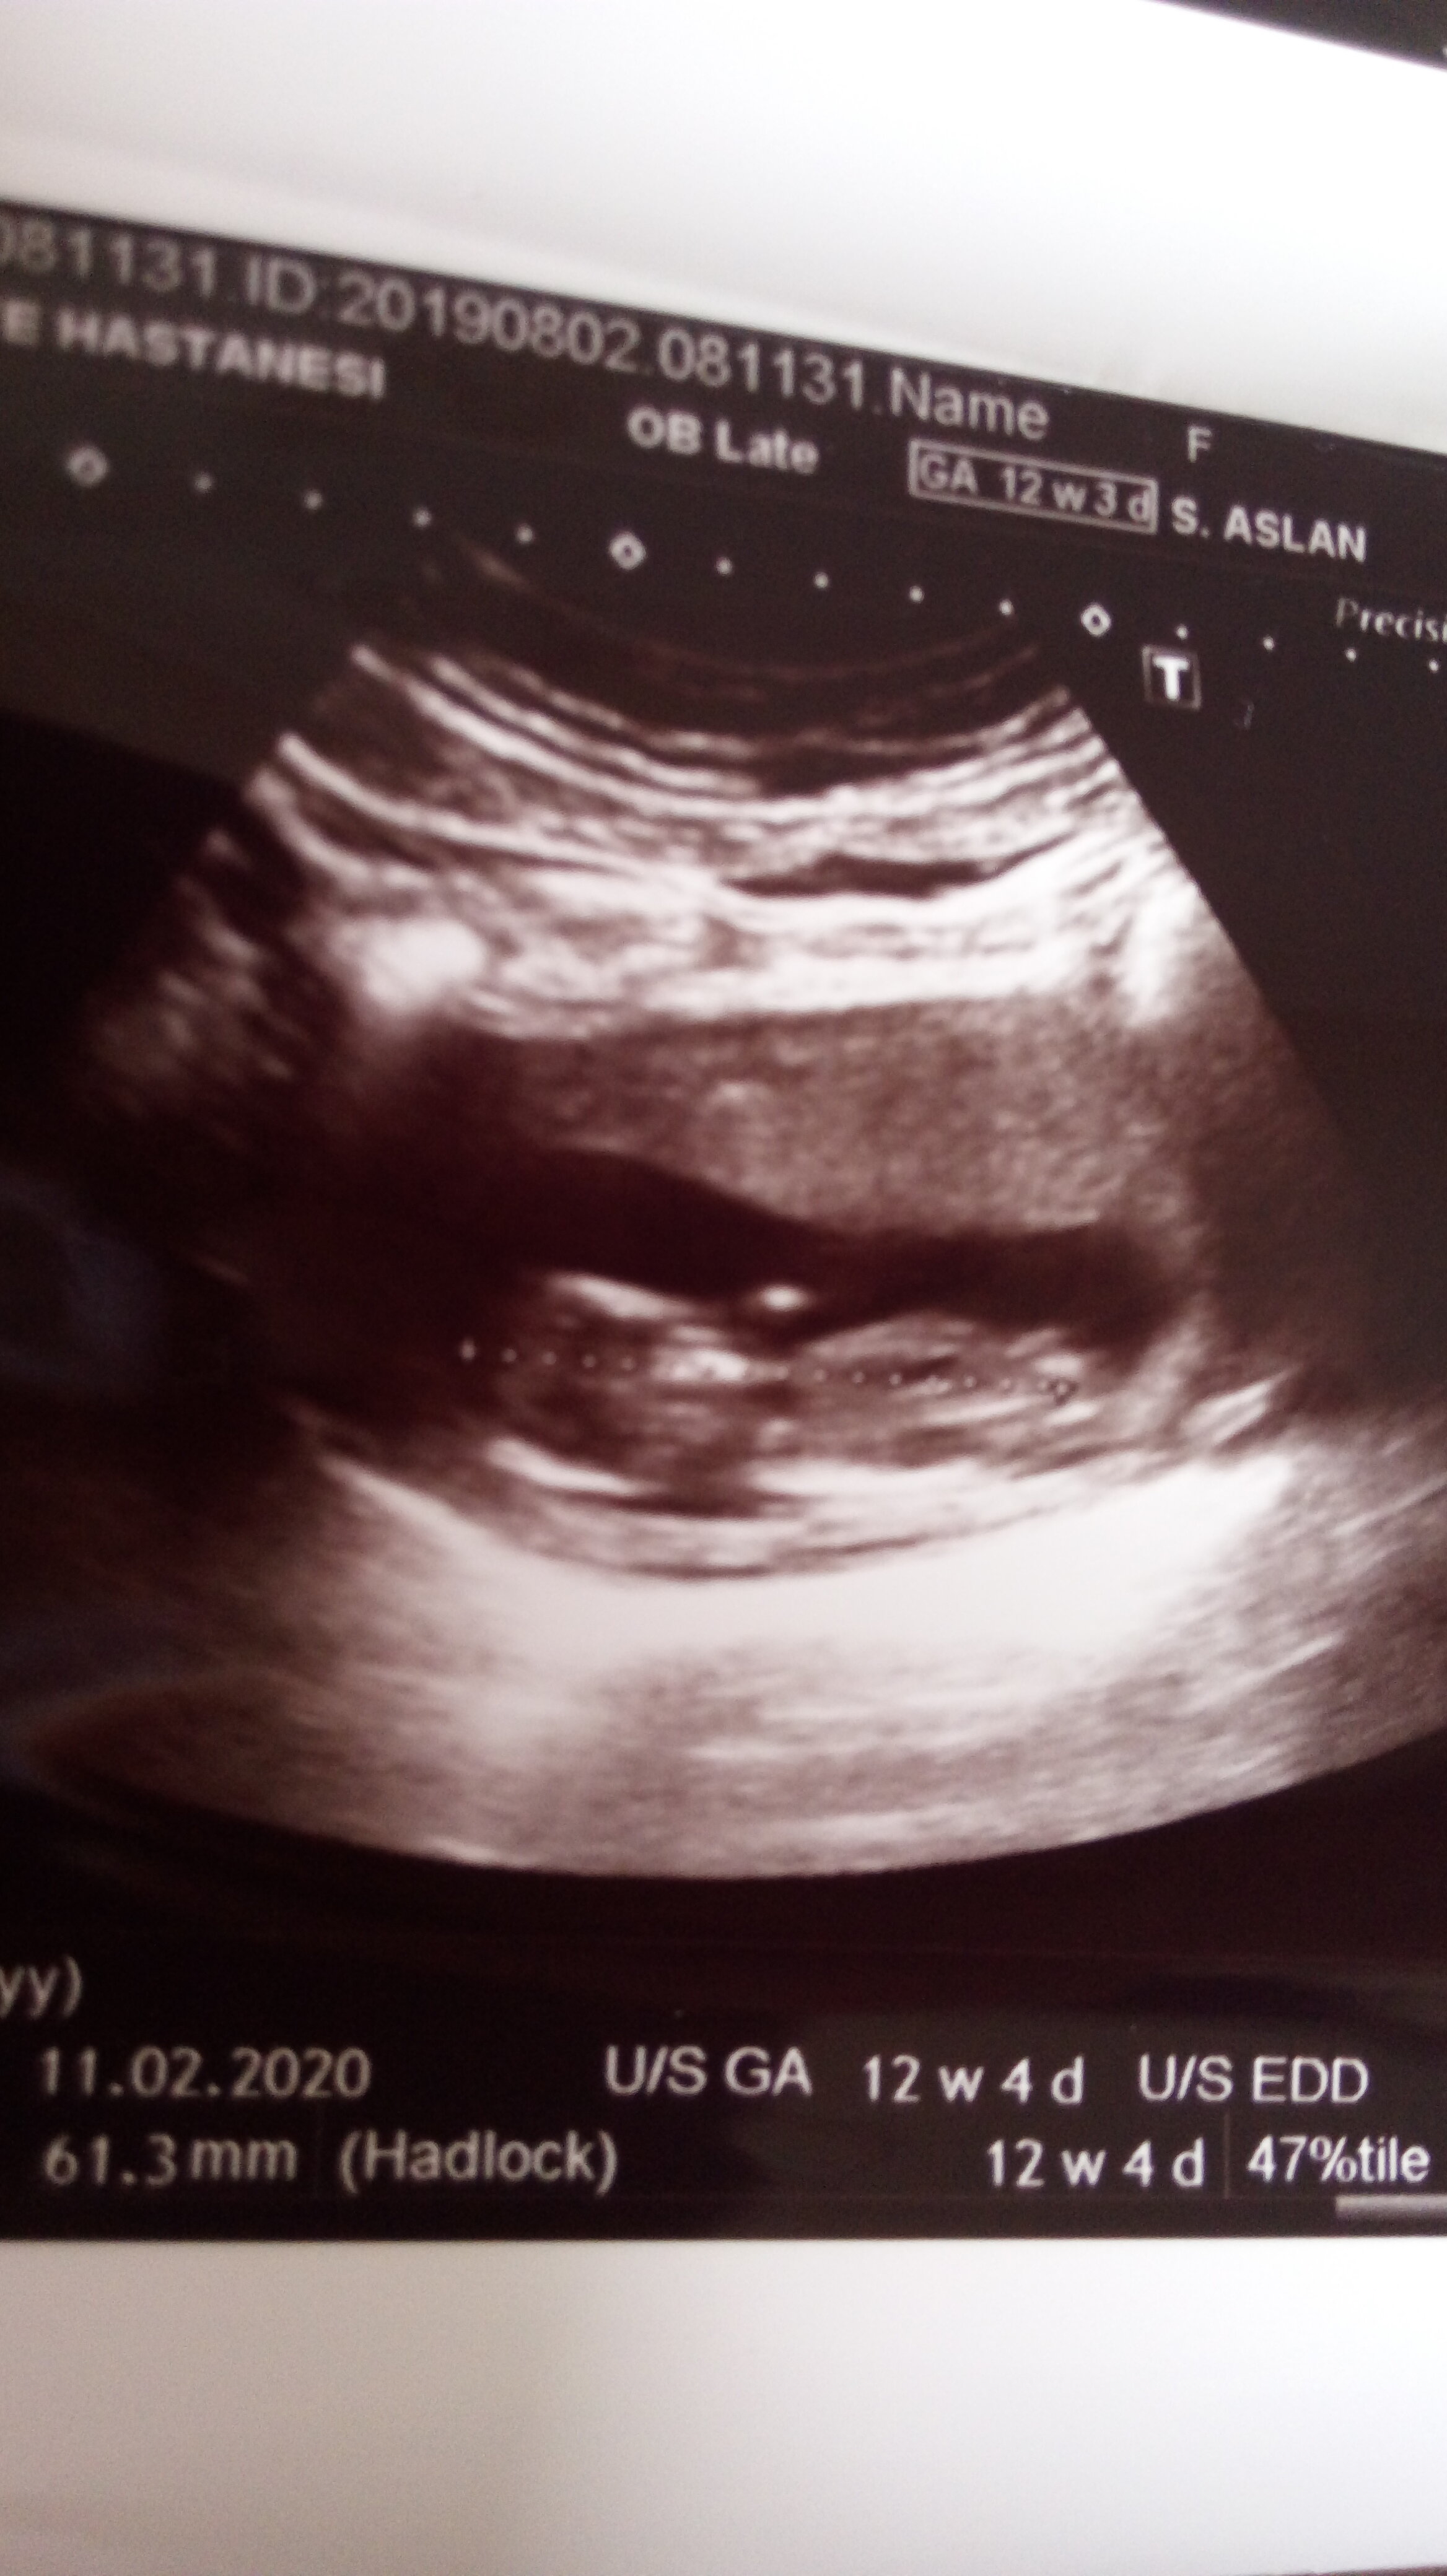

Bakabilirmisiniz nub belli oluyormu cinsiyeti nedir bebeğimin

cinsiyet nedirMerhaba ,

Resim yükleyebilmeniz için üye olmanız gerekiyor. Ayrıca yukarda ki görsel kadar net ise usg görüntünüz yorumlayabilirim.